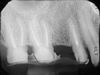

| ENDODONZIA | ||||

| Copyright © Dott.Umberto Romagnoli | ||||